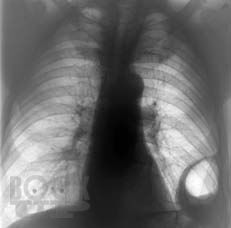

Клинико-рентгенологическая диагностика болезней органов дыхания

Основу данной книги составил архив клинико-рентгенологических наблюдений, собранный авторами в течение ряда лет. Авторы не стремились к подробному описанию клинико-рентгенологической диагностики многочисленных заболеваний бронхолёгочной системы. Материал излагается кратко, почти тезисно и отражает наиболее важные сведения об основной патологии органов дыхания. Цель книги — отражение вопросов клинической картины и рентгенодиагностики распространённых бронхолёгочных заболеваний в условиях муниципальных учреждений здравоохранения с позиции врача общей практики. Предназначено для терапевтов, семейных врачей, студентов медицинских вузов.